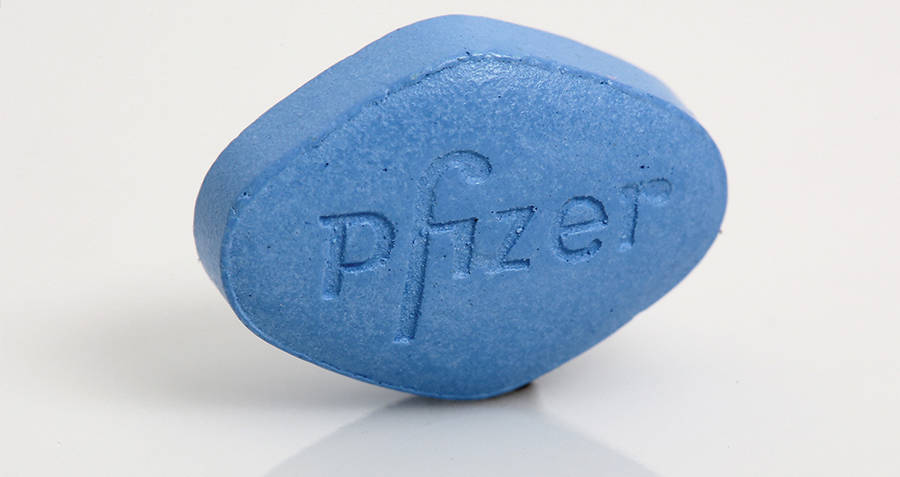

Viagra

Pfizer scientists originally created the drug we know asViagraas a blood pressure medication in 1989. However, during clinical trials in the early 1990s, the drug failed to lower blood pressure. It also, as the male volunteers reported, failed to lower other things. One other thing in particular. As soon as doctors realized that they’d discovered an erectile disfunction drug, the little blue pill penetrated the pharmaceutical industry.